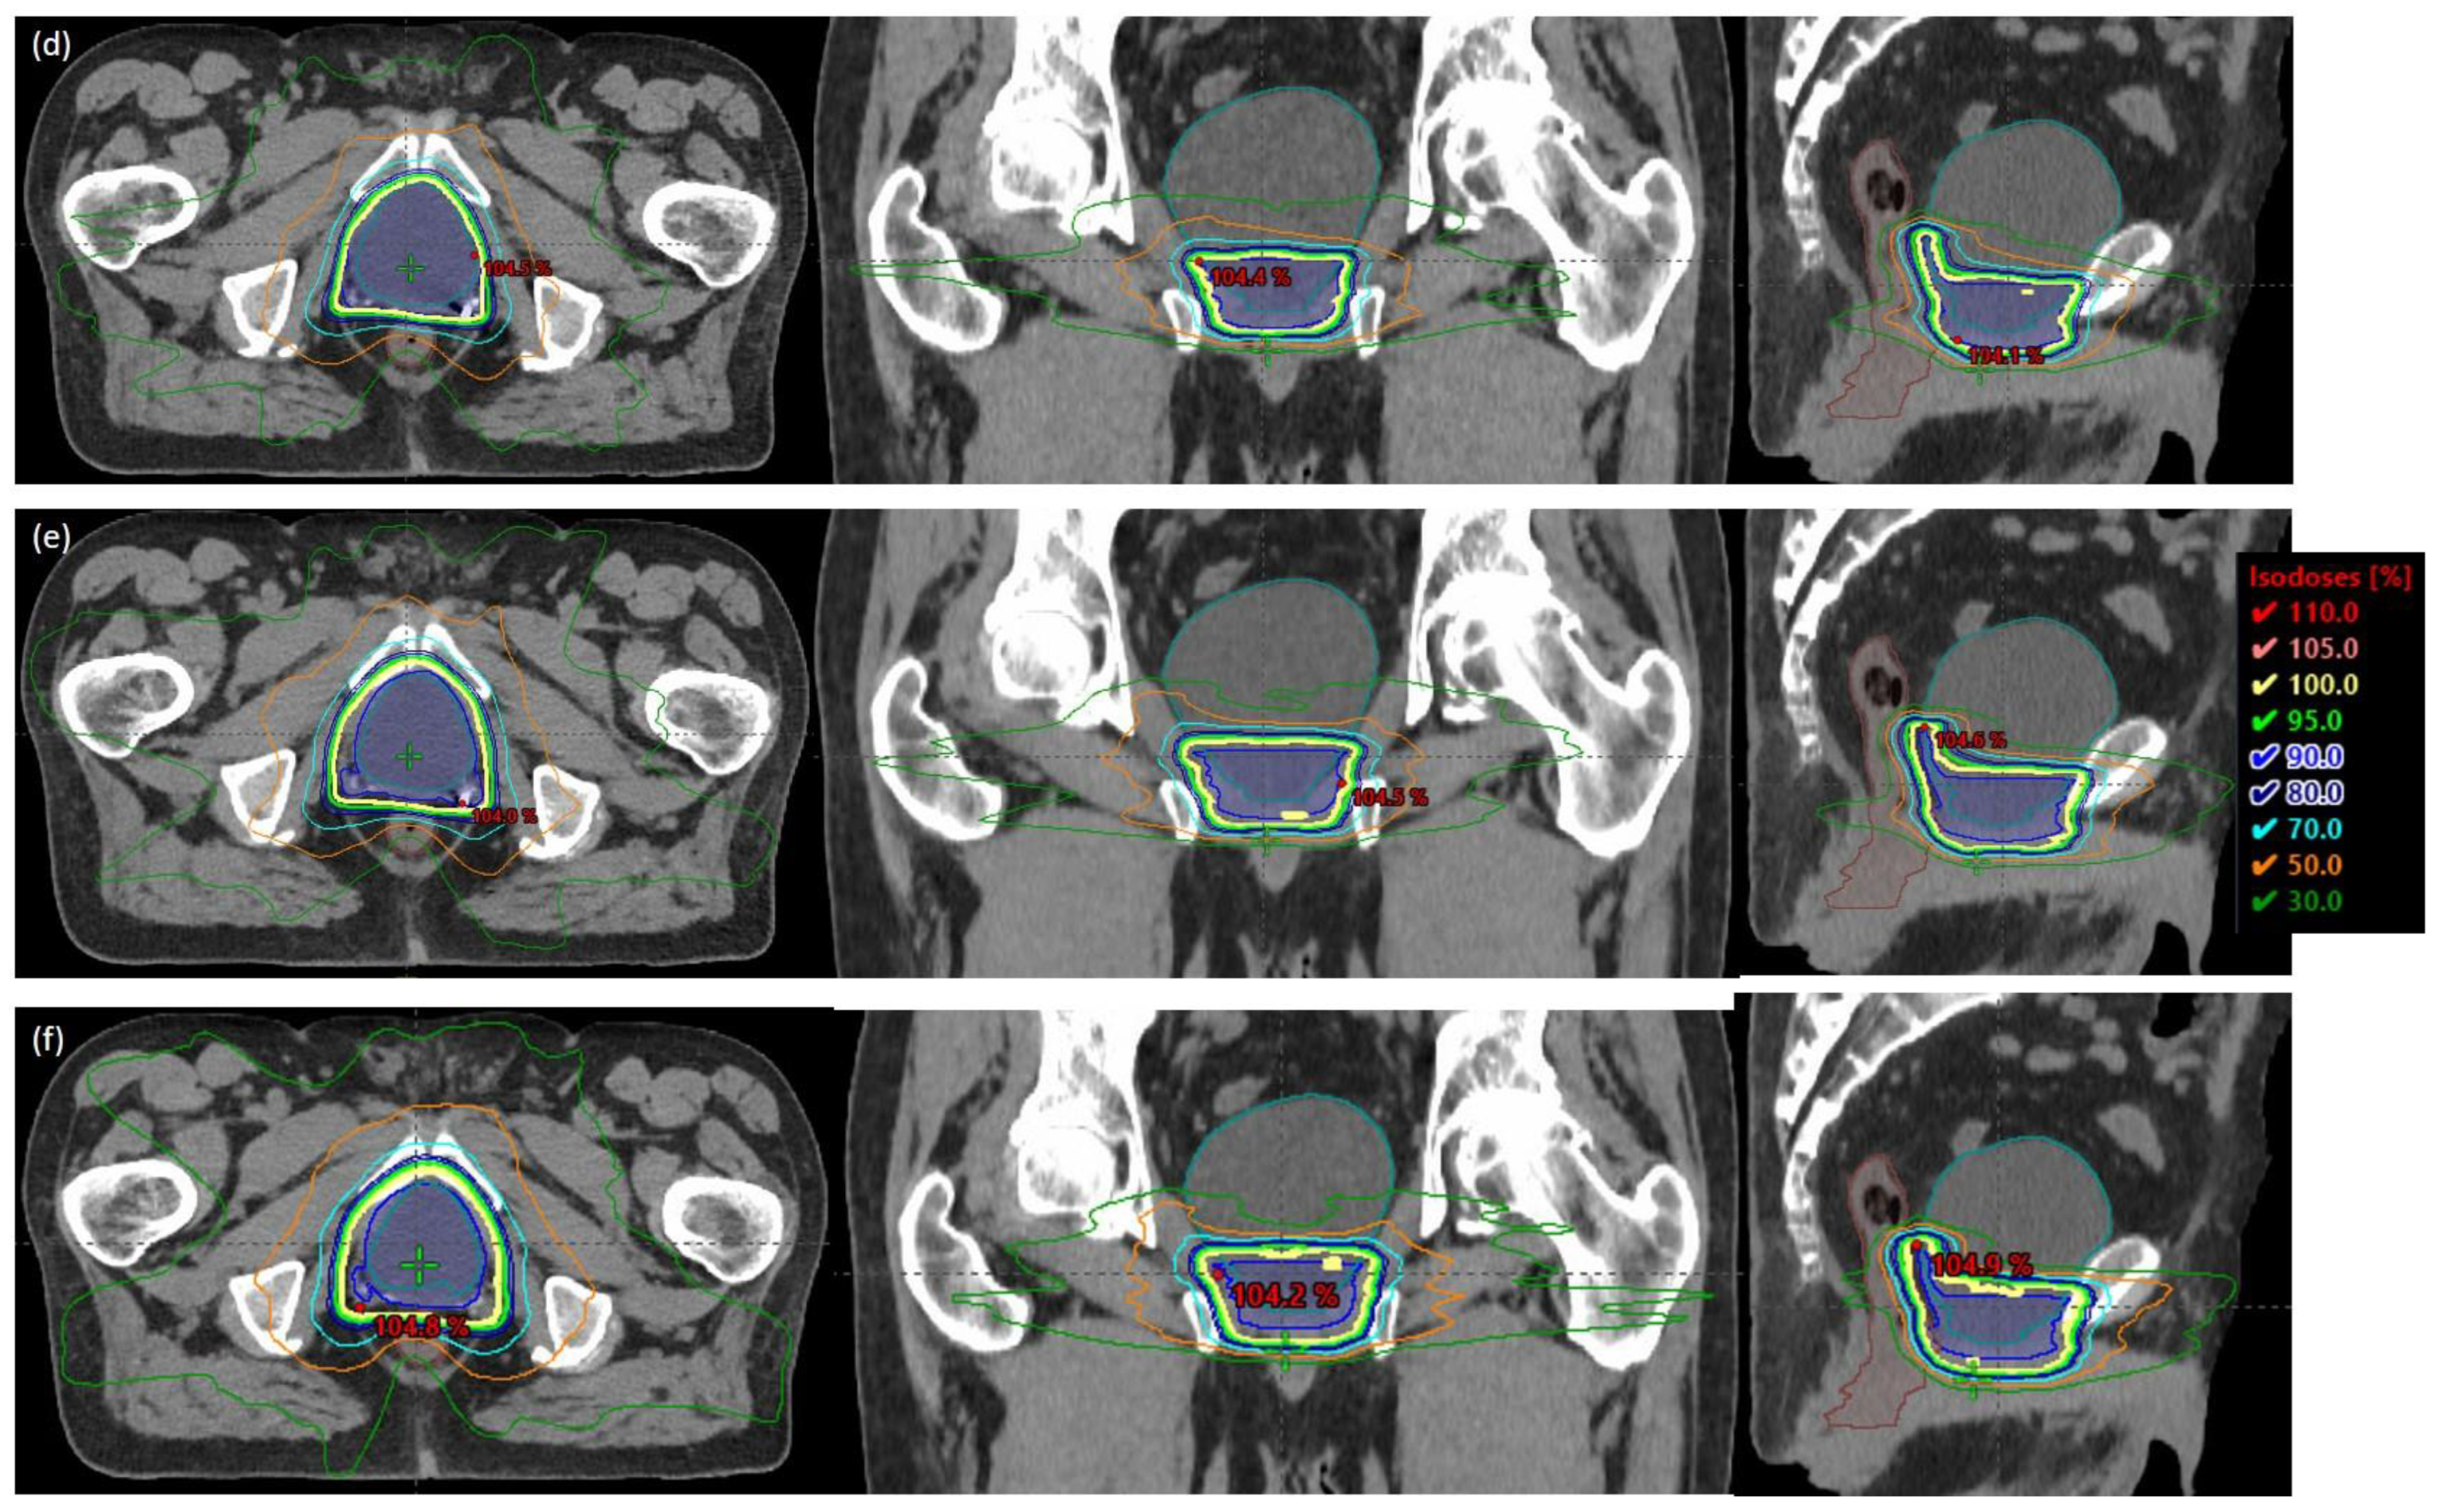

2.1. Patient Characteristics, Simulation, and Planning

2.2. Data Acquisition and Analysis

3. Results